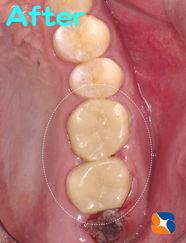

〈写真右〉出発2日前

出発される2日前、セレック器を使用して、セラミックの奥歯2本を製作&装着しました。

私自らが製作するため、噛み合わせもほぼ無調整で完了いたしました。